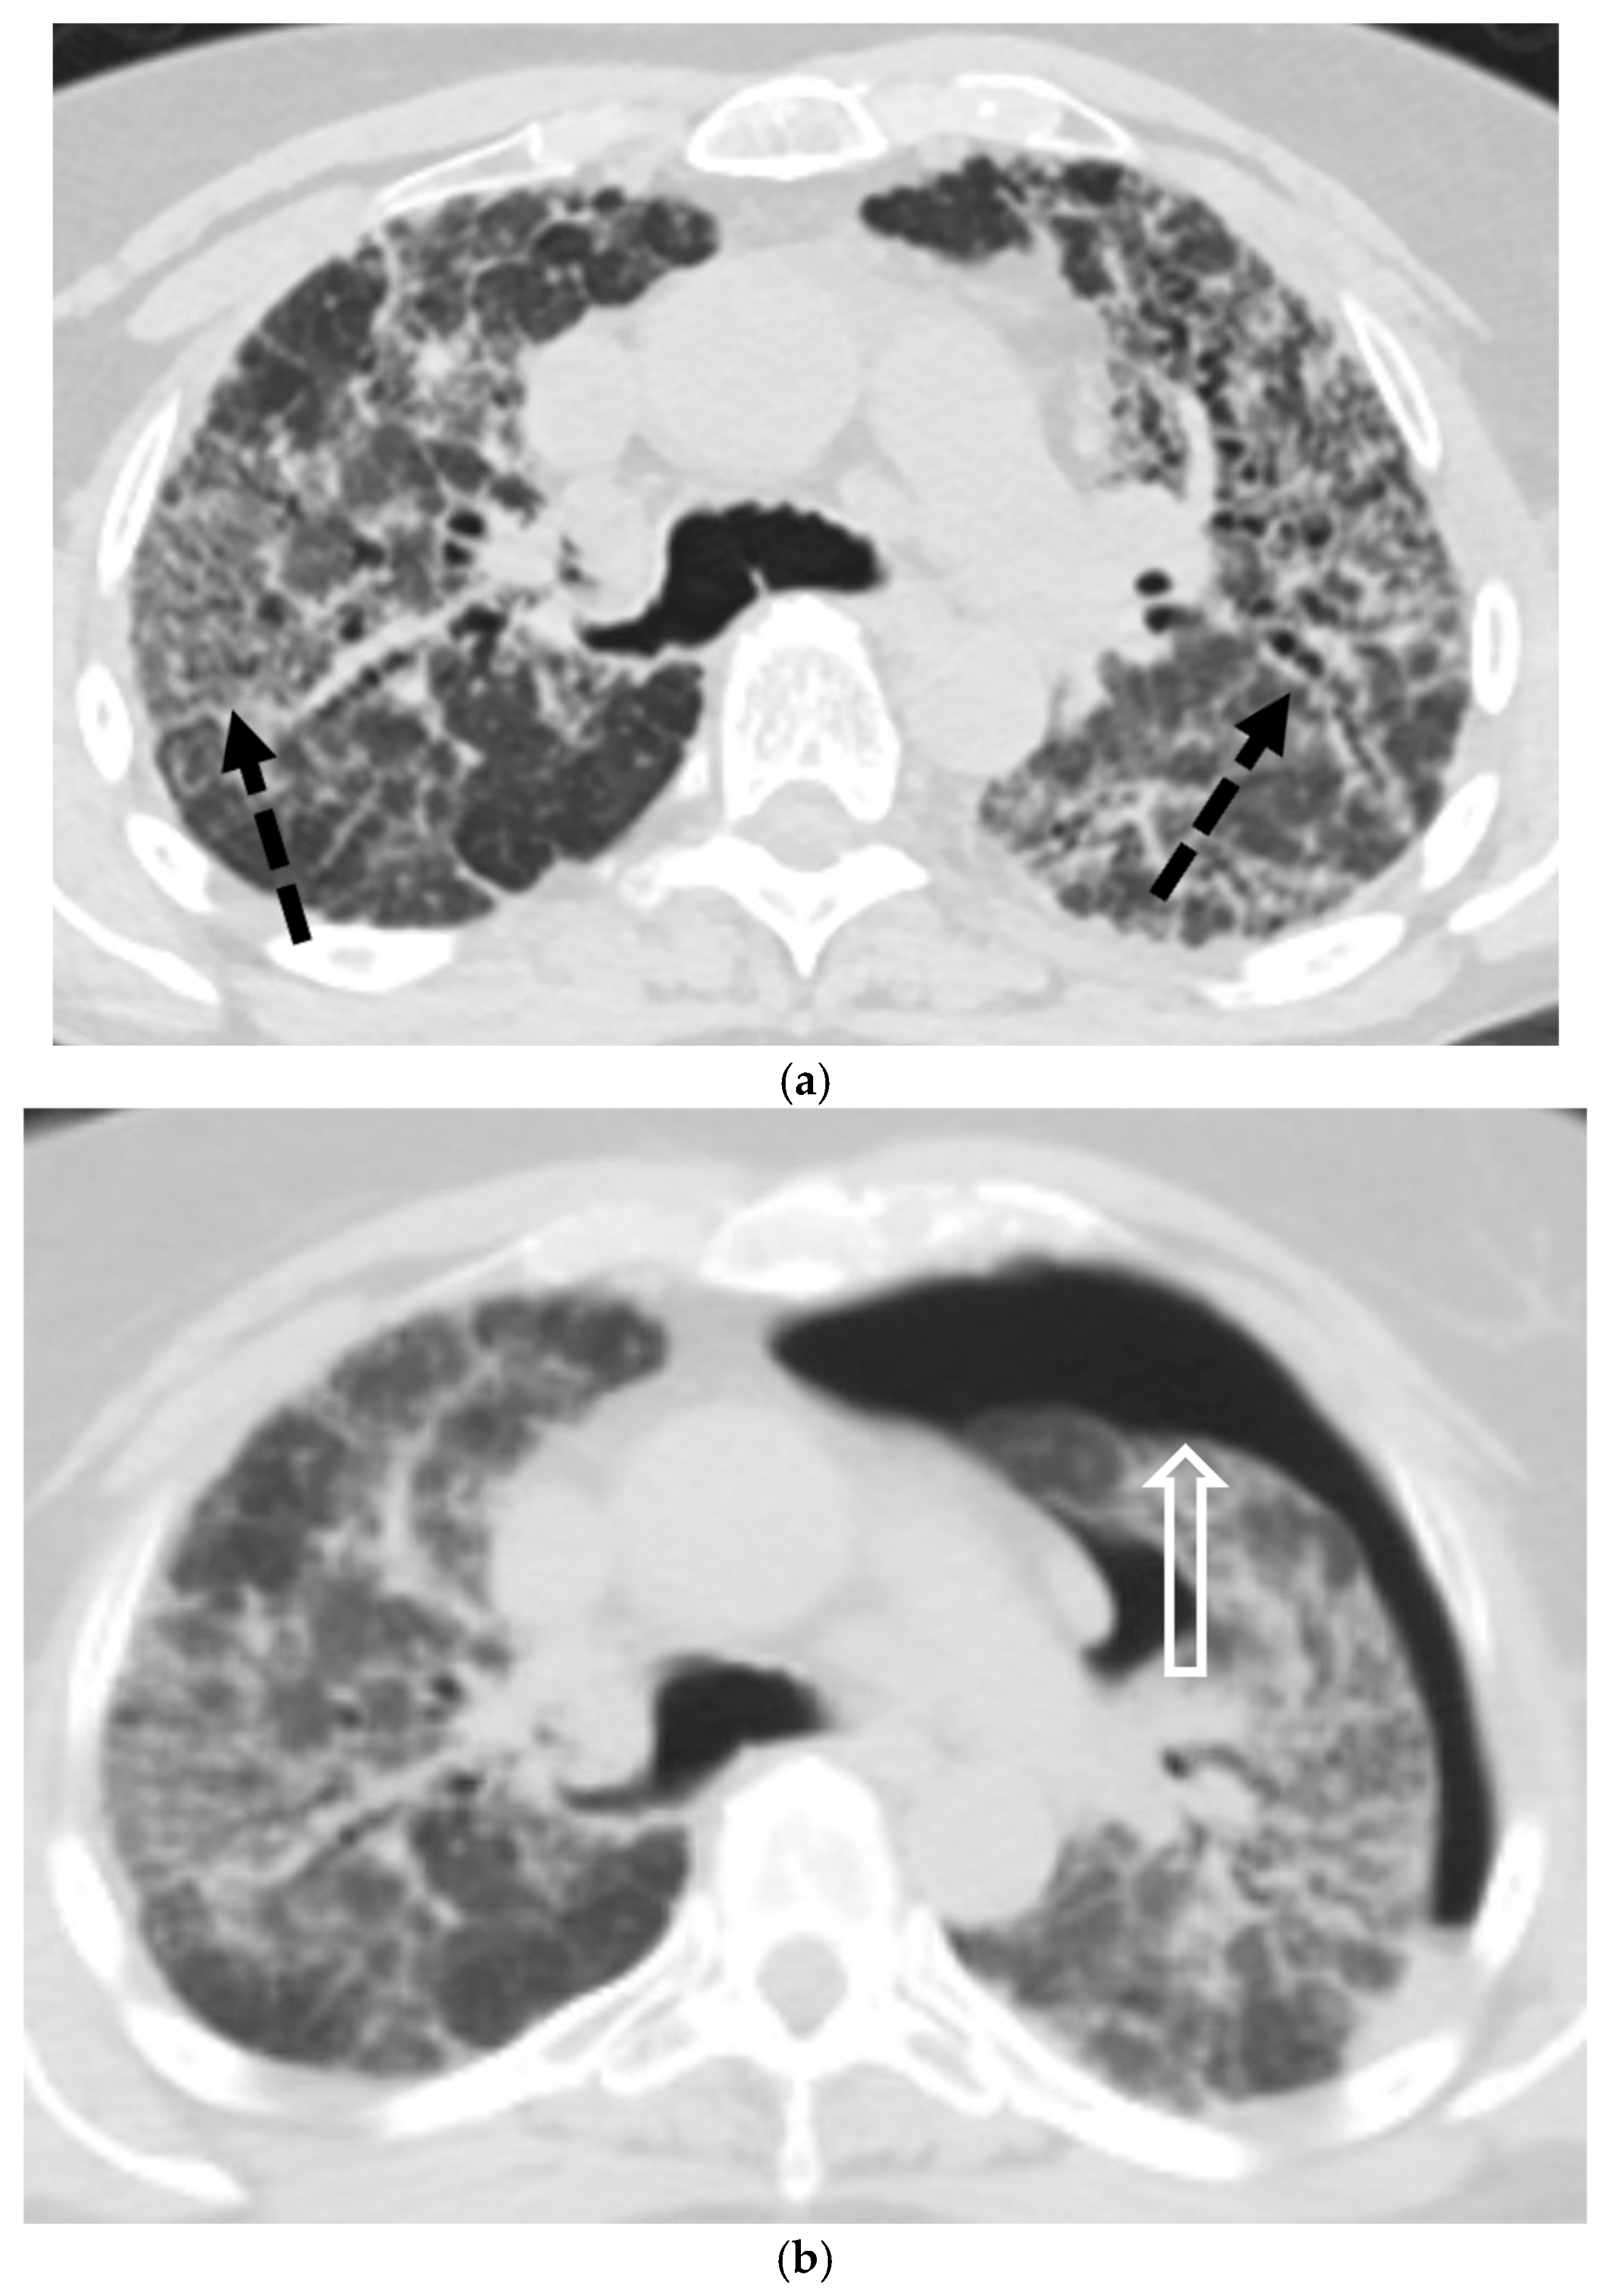

5.3. Malignancies

5.4. Interstitial Lung Diseases (ILDs)

5.4.1. Idiopathic Pulmonary Fibrosis (IPF)